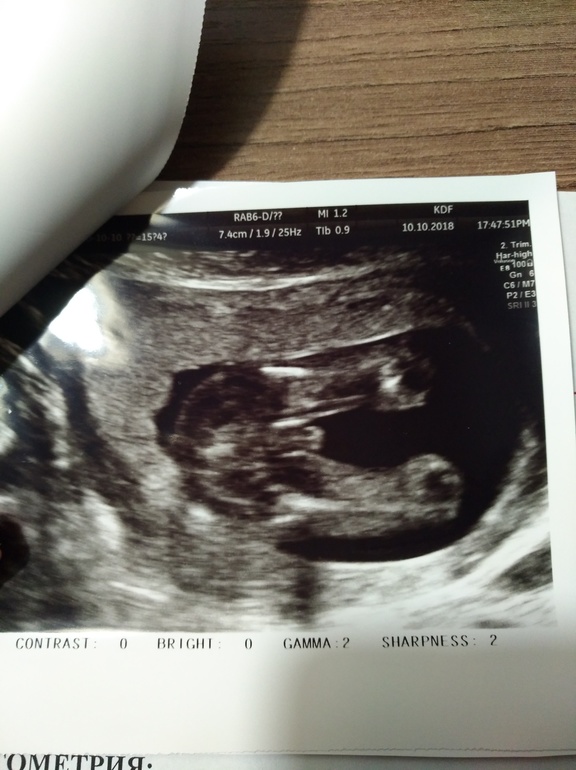

Определение пола

По бокам половые губки, а посредине клитор

Девочка

Нетерпение - оно такое...)) Вопрос о поле малыша.